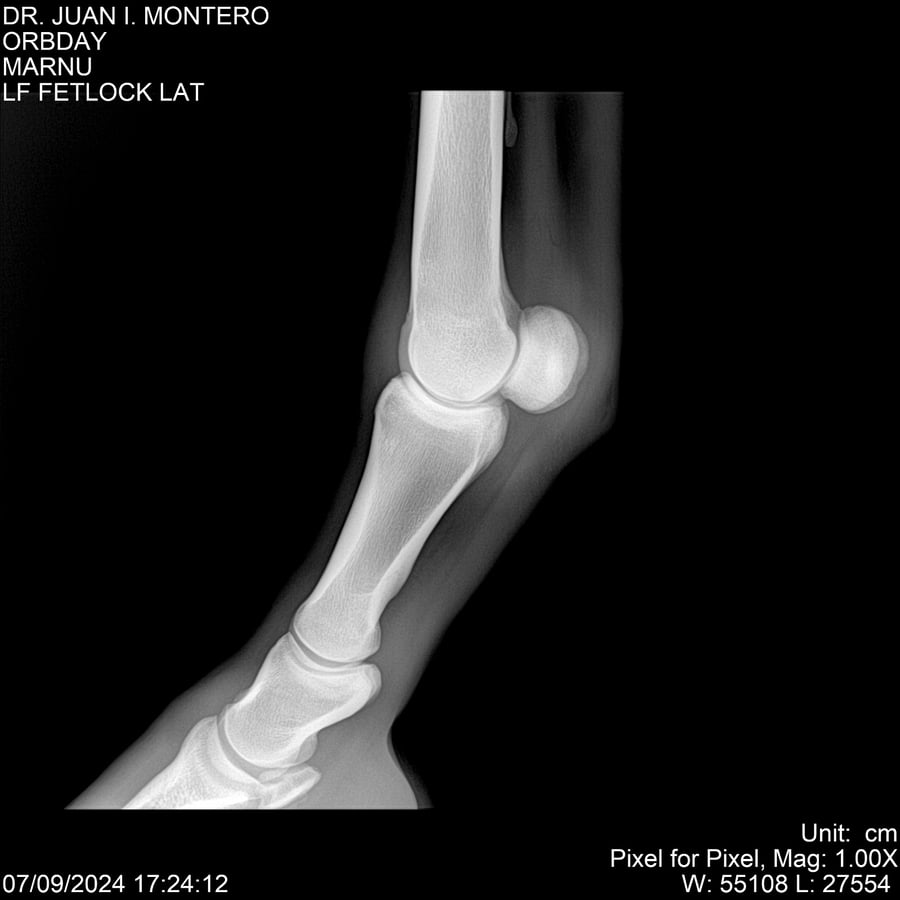

Visualizaciones